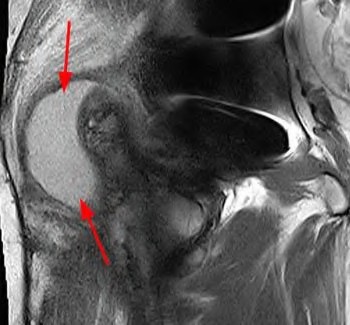

A 75-year-old man underwent total hip arthroplasty 10 years ago. He now reports mild groin pain which has been increasing lately. What is the most likely explanation for the finding in Figure A indicated with the arrows?

1) Osteosarcoma

2) Galvanic corrosion of the modular components

3) Polyethlene wear particles tracking through the effective joint space

4) Joint sepsis

5) Occult fracture

Osteolysis of the pelvis is a common complication associated with total hip arthroplasty. Osteolysis affects sockets with and without cement, and has been attributed to the biologic reaction to wear debris. With well-fixed cementless sockets, an expansile pattern of osteolysis is usually seen.

The radiographic appearance has a radiolucent area that starts at the implant-bone interface and expands into the cancellous bone away from the implant.

This pattern of osteolysis can be explained with the concept of effective joint space. This concept states that joint fluid and wear particles will flow according to pressure gradients and follow the path of least resistance.

The Level 5 review article by Chiang discusses osteolysis in further depth.